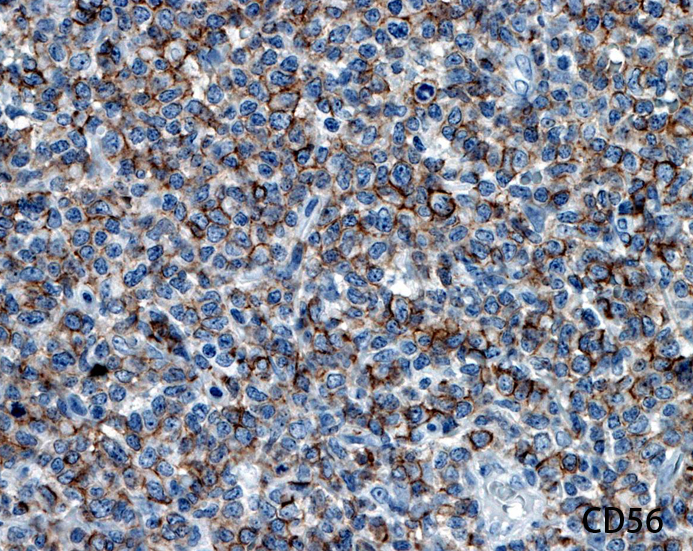

Fig03, Fig04は腫瘍細胞の拡大像。大型異型細胞の出現が認められる。腫瘍細胞はCD4+, CD56+, CD123+

この頃はCD4+, CD56+ にCD123陽性で診断が可能であったが, 他疾患でもこの陽性パターンをとることがわかってきた.